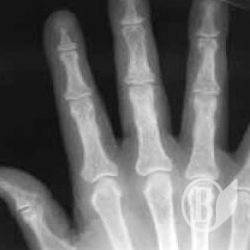

В милицию обратилась 70-летняя черниговчанка. Она сообщила, что её сын, который проживает с ней, нанёс ей телесные повреждения в виде перелома всех пальцев правой руки.

По результатам судебно-медицинской экспертизы такие повреждения принадлежат к средней степени тяжести.